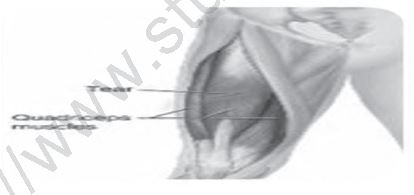

DISLOCATION

Dislocations are joint injuries that force the ends of your bones out of position. The cause is often a fall or a blow, sometimes from playing a contact sport. A joint dislocation, also called luxation, occurs when there is an abnormal separation in the joint, where two or more bones meet. A partial dislocation is referred to as a subluxation. Dislocation can be caused by a trauma (accident or fall) or the weakening of muscles and tendons. A dislocated joint can be treated through medication, manipulation, rest or surgery.

Causes - Trauma that forces a joint out of place causes a dislocation. Accidents, falls, and contact sports such as football are common causes of this injury. Dislocations also occur during regular activities when the muscles and tendons surrounding the joint are weak. These injuries happen more often in older people who have weaker muscles and balance issues.

Symptoms - Symptoms of a dislocation vary depending on the severity and location of the injury. The symptoms of a dislocated joint include:

• Pain

• Swelling

• Bruising

• Instability of the joint

• Loss of ability to move the joint

• Visibly deformed joint (bone looks out of place)

Treatment - Treatment can vary based on the severity of the injury, and the joint that is dislocated. Applying ice and keeping the joint elevated can help reduce pain while you wait to see a doctor. Treatment includes:

• Medication: Your doctor may recommend medication to reduce pain from a dislocation

• Manipulation: A doctor returns the bones to their proper places.

• Rest: Once the joint is back in place, you may need to protect it and keep it immobile. Using a sling or splint can help the area heal fully.

• Rehabilitation: Physical therapy exercises strengthen the muscles and ligaments around the joint to help support it.

• Surgery: Your doctor may recommend surgery if:

• Manipulation does not work to put the bones back in place.

• The dislocation damaged blood vessels or nerves.

• The dislocation damaged bones, tore muscles or ligaments that need repair.